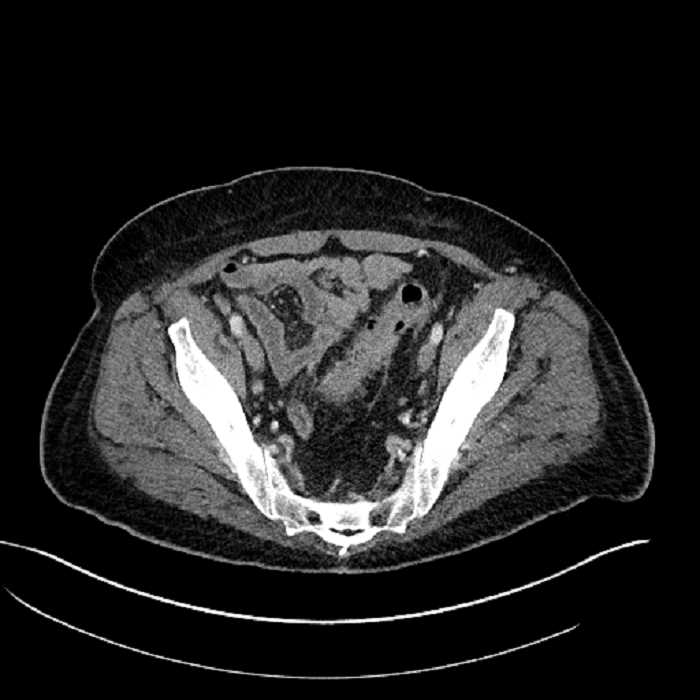

Age: 63

Sex: Male

Indication: Abdominal pain

• Large fluid density structure in hepatic segments 7 and 8 measuring 10 x 7 x 7 cm with internal septation and circumferential ill-defined low density compatible with edema

• Peripherally enhancing subcapsular collections along the anterior margin of the left hepatic lobe measuring 3 x 1 cm and 2 x 1 cm

• Clearly marginated fluid density structure in segment 7 and several other scattered tiny hypodensities, which likely represent cysts

• Mild mural thickening of a segment of the sigmoid colon with adjacent fat stranding and a 1.5 cm fluid and gas collection along the tip of an inflamed diverticulum

• Loss of the normal fat plane between this collection and adjacent loops of small bowel, which demonstrate mural thickening

• High grade stenosis of the left common iliac artery, with the left internal and external iliac arteries remaining patent

Acute sigmoid diverticulitis complicated by a small contained perforation and a large abscess in the right hepatic lobe. Additional small subcapsular abscesses along the anterior margin of the left hepatic lobe.

Additionally, loss of the normal fat plane between the peridiverticular collection and adjacent thickened loops of small bowel raises the potential for an enterocolonic fistula.

High grade stenosis of the left common iliac artery. The left external and internal iliac arteries are patent.

Hepatic abscess showing the double target sign with low density internally surrounded by a thin inner enhancing rim (red arrow) and ill-defined outer low density rim (yellow arrow). Blue arrow indicates an internal septation. Red arrows: additional smaller subcapsular abscesses. Red arrow: focal contained perforation associated with diverticulitis.